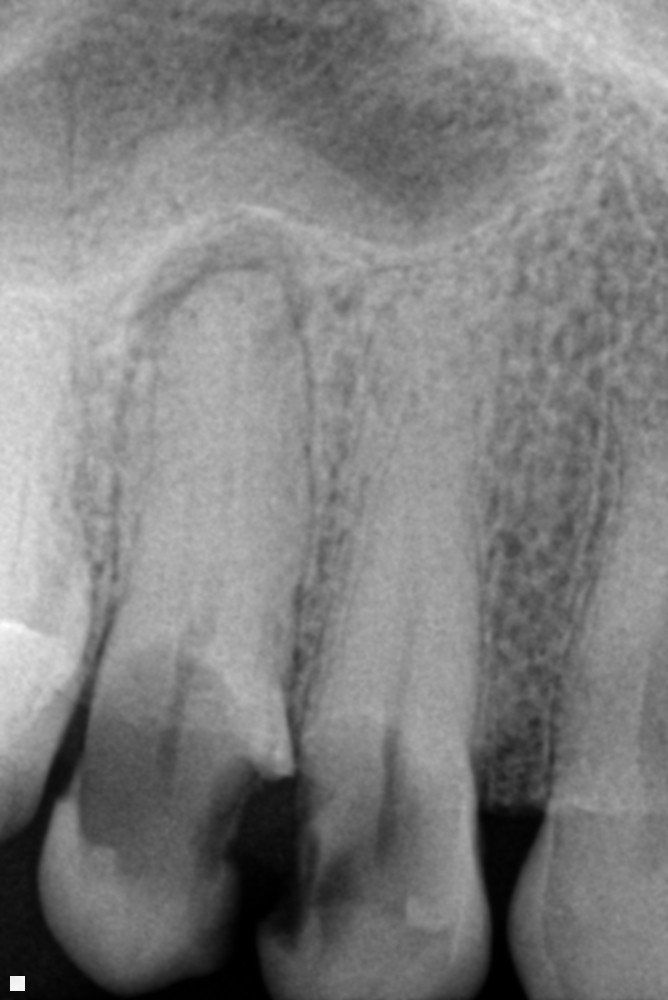

Endodonzia

Tra le mie competenze ci sono quelle specifiche per il settore dell’endodonzia.

Si tratta di una branca dell'odontoiatria che ha come principale obiettivo quello di procedere alla terapia di patologie che colpiscono l'endodonto ossia quello spazio presente all'interno dell'elemento dentario.

L'endodonzia è importantissima perché consente di prevenire ed eliminare dolori poiché, nella polpa dentaria, son presenti vasi e terminazioni nervose.

Tutto questo viene affrontato con le più moderne tecniche che permettono minima invasività e risultato in tempi ristretti.